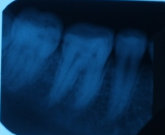

На каких зубах существует вероятность пульпита? 2. Есть ли вероятность, что на снимке присутствуют зубы, такие, что зуб значительно разрушен (от четырёх поверхностей), поэтому здесь требуется восстановление. То есть речь идёт о ситуации кариеса, когда пострадало более трёх поверхностей. Как известно, любой зуб имеет пять поверхностей (1. С внешней стороны. 2. С внутренней стороны (со стороны языка). 3. Со стороны левого соседнего зуба. 4. Со стороны правого соседнего зуба. 5. С жевательной стороны. Я понимаю, что точно диагноз нельзя поставить только по снимку, потому что нужен и визуальный осмотр, но речь идёт просто о возможности (подозрительных зубах и наиболее сложных).

Прям четких пульпитных явлений на снимке я не увидел. Шестой зуб сверху (26), требует установки коронки из-за большого количества пломбы, что по показаниям требуется реставрация вкладкой и коронкой. Не знаю про какой зуб идёт речь, но при разрушении коронковой части зуба более, чем на 50%, необходимо устанавливать коронки. Для более подробной консультации, обратитесь к стоматологу на очный приём.